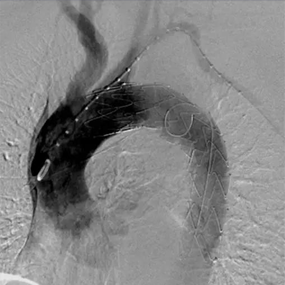

Hercules®/通天杖™Low Profile直管型覆膜支架及输送系统

Hercules®/通天杖™ Low Profile直管型覆膜支架及输送系统临床上用于瘤体局限于血管直管段的多种型式的主动脉瘤的治疗。